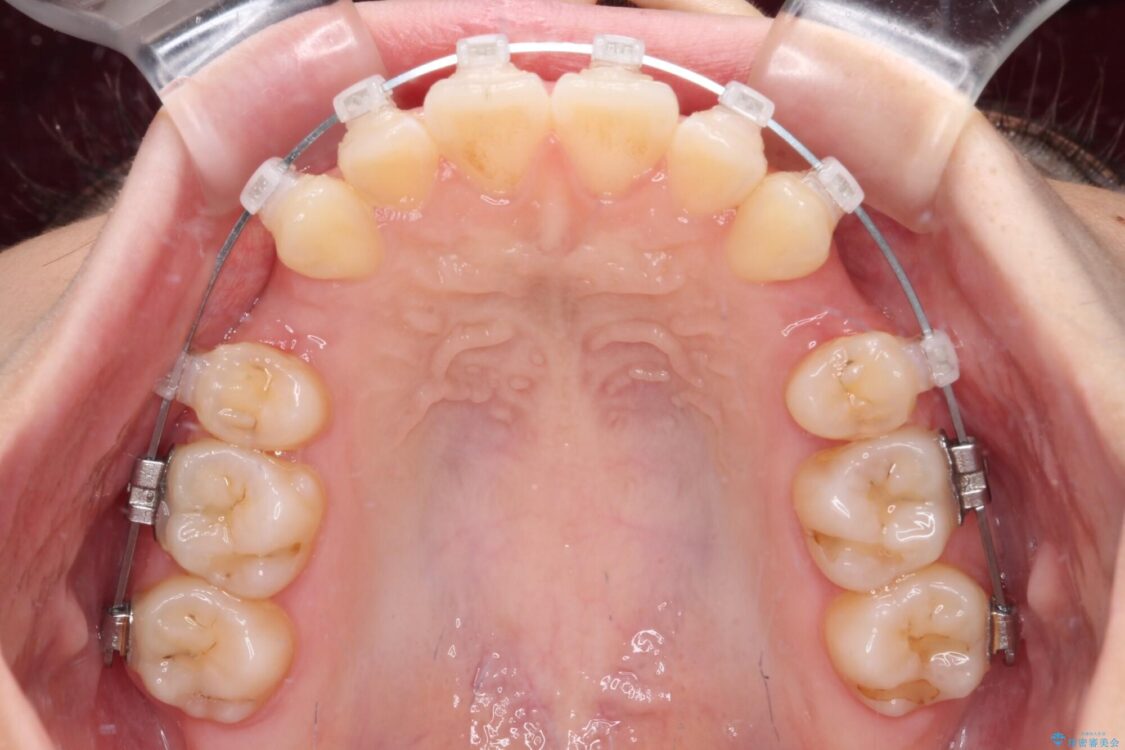

治療途中

• 【モニター】口が閉じられない ワイヤー装置での抜歯矯正 治療途中画像

※写真にある上顎装置はメタルブラケットではありません。メーカー在庫都合などにより別の装置を使用しております。